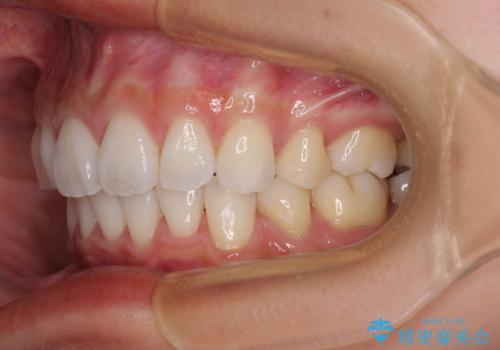

尖った前歯を引っ込めたい 目立たないワイヤー装置での抜歯矯正

- 飛び出した前歯を気にして来院された患者様です。

口元を引っ込めるために上下左右の第一小臼歯4本を抜歯することとしました。

結婚式を行う予定があるとのことで、表側のワイヤー装置で、速やかに治療を終えられるようにしました。

途中妊娠と出産がありましたが、予定よりも早く治療を終えることができました。